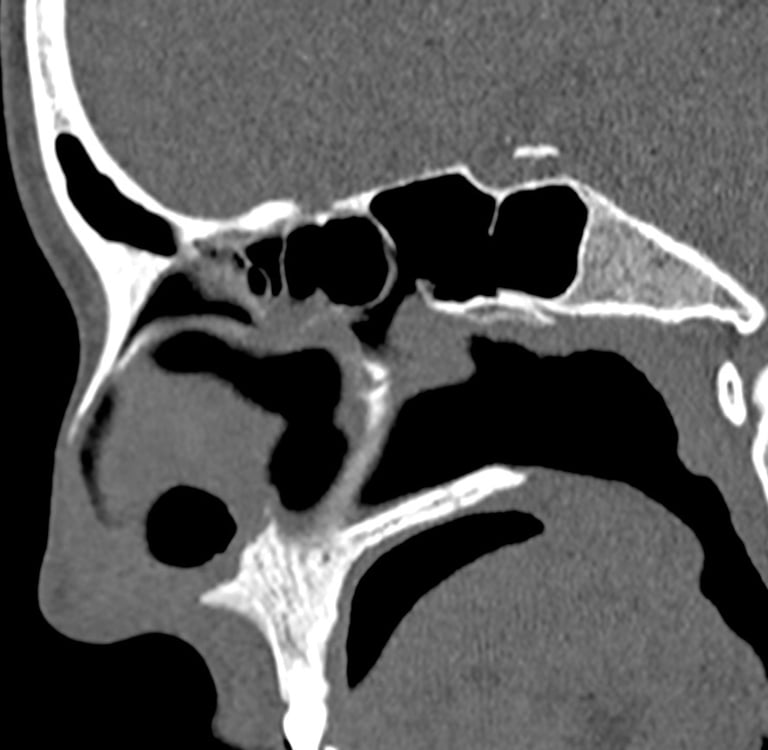

Perforacija septuma jedna je od poznatih, ali relativno rijetkih komplikacija operacija nosa. Najčešće se povezuje sa septoplastikom, ali može nastati i nakon rinoplastike ili endoskopske kirurgije sinusa.Iako je učestalost mala, posljedice mogu biti dugotrajne i funkcionalno značajne – osobito ako se defekt nalazi u prednjem dijelu septuma.

Nosna pregrada obložena je sluznicom s obje strane. Tijekom operacije kirurg pažljivo odvaja sluznicu kako bi ispravio devijaciju ili pristupio dubljim strukturama.

Hrskavica septuma nema vlastitu krvnu opskrbu – ovisi o sluznici. Ako obje strane sluznice izgube vitalnost, dolazi do nekroze hrskavice i stvaranja trajnog defekta.